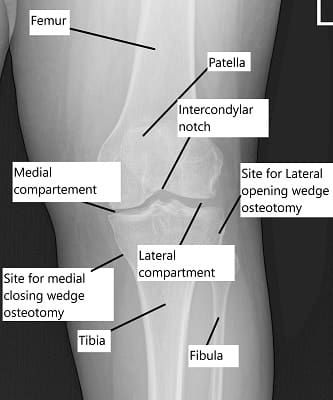

X-ray showing the knee joint

In a normal individual the thigh bone and shin bone are aligned so the weight is transmitted equally among the inner and the outer side of the joint. Any malalignment or mismatch leads to excessive weight being placed on one side of the knee. With repetitive loading parts of the cartilage and meniscus get torn on the side placed under undue force. Bow legs or knock knees are examples of malalignment.